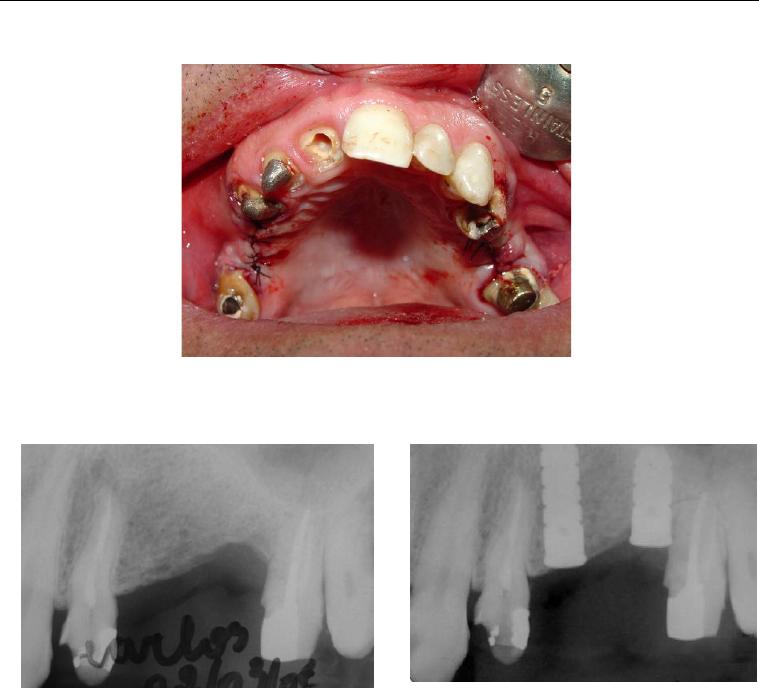

Foi no intuito de transpor estas dificuldades que se idealizou o sistema de

implante inicialmente conhecido como Wedge (figura 1) e que, após dez anos de